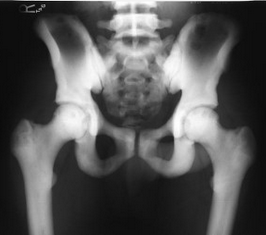

A 31 year old female takes a spill while skiing and can’t get up. You see her in the ED laying like this and promptly relocate her hip. What motor tests should you do when assessing her for nerve injury?

She may have injured the superior or inferior gluteal nerve, which is vulnerable in a posterior hip dislocation. This will result in a positive Trendelenberg’s test (superior gluteal nerve injury), an inability to abduct the thigh (superior gluteal nerve injury) or rise from a seated position (inferior gluteal nerve injury).